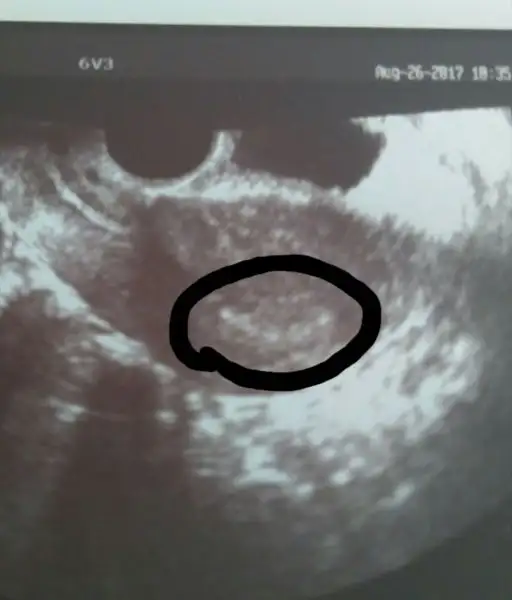

Şimdi aradı Dr. Keseyi bu gidişata göre arefe günü görebiliriz dedi.